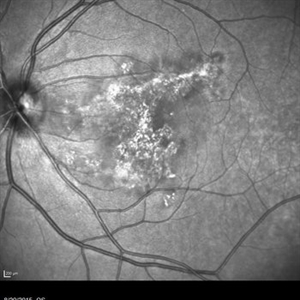

Fluorescein angiography of an 18-year-old with macular serpiginous choroidopathy.

Photographer: Phylicia Yanna, Retina Eye Center, Eye Associates of Northeast Louisiana

Imaging device: Heidelberg Spectralis

Condition/keywords: macula serpiginous choroidopathy